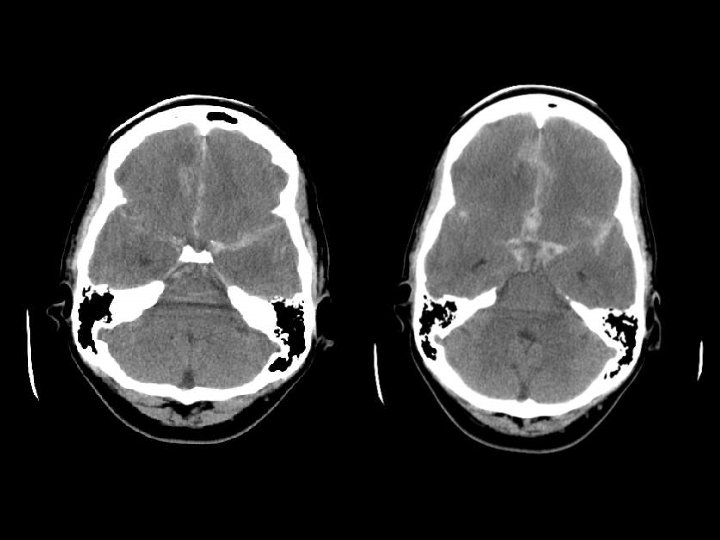

Perdarahan Intraventricular n Paling sering akibat ruptur pembuluh darah subependymal n Dapat timbul akibat refluks dari SAH atau perluasan dari perdarahan intraserebral n Lihat adanya blood-cerebrospinal fluid level di occipital horns

Subarachnoid hemorrage n Dapat timbul dari jejas langsung ke pembuluh darah, contused cortex atau perdarahan intraventricular n Lihat pada sisterna interpeduncular dan fisura Sylvii n Biasanya focal (namun dapat difus kalau berasal dari aneurisma) n Dapat menyebabkan communicating hydrocephalus

Kumpulan cairan ekstraaksial n Subarachnoid hemorrhage(SAH) n Subdural hematoma(SDH) n Epidural hematoma n Subdural hygroma n Intraventricular hemorrhage